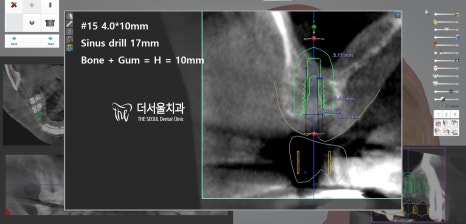

『# 14 # 15 # 46 implant

디지털 방식의 분석을 이용하여

식립 방향 및 각도를 결정하고

최종적으로 심어질 위치까지 선정했습니다.

이후 계산된 곳에 튼튼한 픽스처를 심어드렸죠.